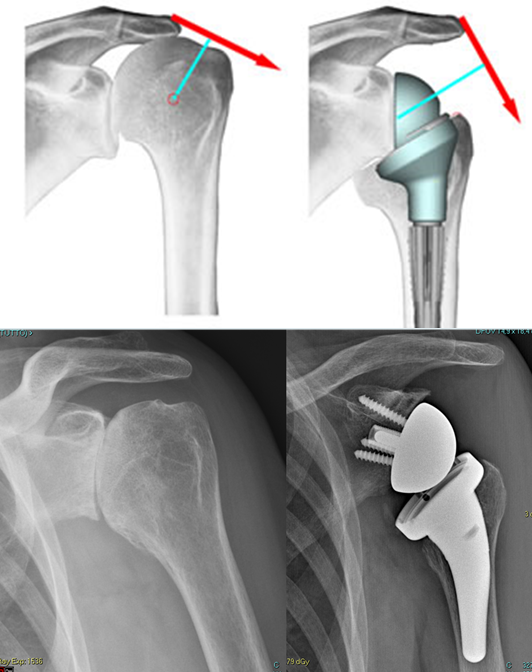

Protesi inversa – Un altro modello di protesi totale che si è andato affermando negli anni più recenti e che merita un discorso a parte è la cosiddetta “protesi inversa” (fig. 14).

Tale impianto porta questo nome perché le geometrie sono rovesciate rispetto all’articolazione naturale: alla scapola viene fissata una componente convessa, semisferica, mentre la superficie concava si trova sul versante dell’omero. Per ragioni biomeccaniche complesse questo sistema è indicato nei casi in cui la funzione della cuffia dei rotatori è compromessa per lesione massiva irreparabile. In queste situazioni gli altri tipi di protesi non permetterebbero di recuperare un soddisfacente movimento attivo. Per la funzionalità della protesi inversa condizione indispensabile è che il deltoide sia efficiente.

La protesi inversa è indicata in genere in pazienti non più giovani, la cui cuffia dei rotatori presenta una vasta lesione, o che magari è così degenerata da lasciare supporre che nel volgere di pochi anni andrà incontro a lesione massiva.